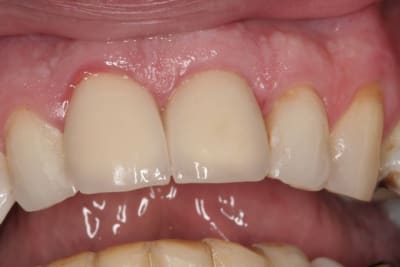

le hasard fait parfois bien les choses...patient revu ce matin pour une "bricole" sur une restauration postérieure...

il est intéressant de voir la maturation des tissus mous...et en plus VS des différences au niveau de l'hygiène, pas mal secteur 2 mais perfectible secteur 1...

ici on est à 3 mois post pose prothèses d'usage...la photo, prise un peu décalée, donne l'impression d'une différence de hauteur des collets, mais il n'en est rien (ou alors très peu...)

quand même content du résultat...;-) même si j'ai (lourdement)insisté pour que l'hygiène soit un peu mieux suivie...